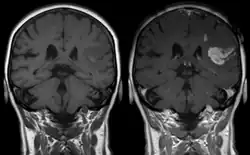

Gadolinium(III) containing MRI contrast agents (often termed simply "gado" or "gad") are the most commonly used for enhancement of vessels in MR angiography or for brain tumor enhancement associated with the degradation of the blood–brain barrier (BBB).[3][4] Over 450 million doses have been administered worldwide from 1988 to 2017.[5] For large vessels such as the aorta and its branches, the dose can be as low as 0.1 mmol/kg of body mass. Higher concentrations are often used for finer vasculature.[6] At much higher concentration, there is more T2 shortening effect of gadolinium, causing gadolinium brightness to be less than surrounding body tissues.[7] However at such concentration, it will cause greater toxicity to bodily tissues.[8]

Gd3+ chelates are hydrophilic and do not readily cross the intact blood–brain barrier. Thus, they are useful in enhancing lesions and tumors where the blood–brain barrier is compromised and the Gd(III) leaks out.[9][lower-alpha 1] In the rest of the body, the Gd3+ initially remains in the circulation but then distributes into the interstitial space or is eliminated by the kidneys.